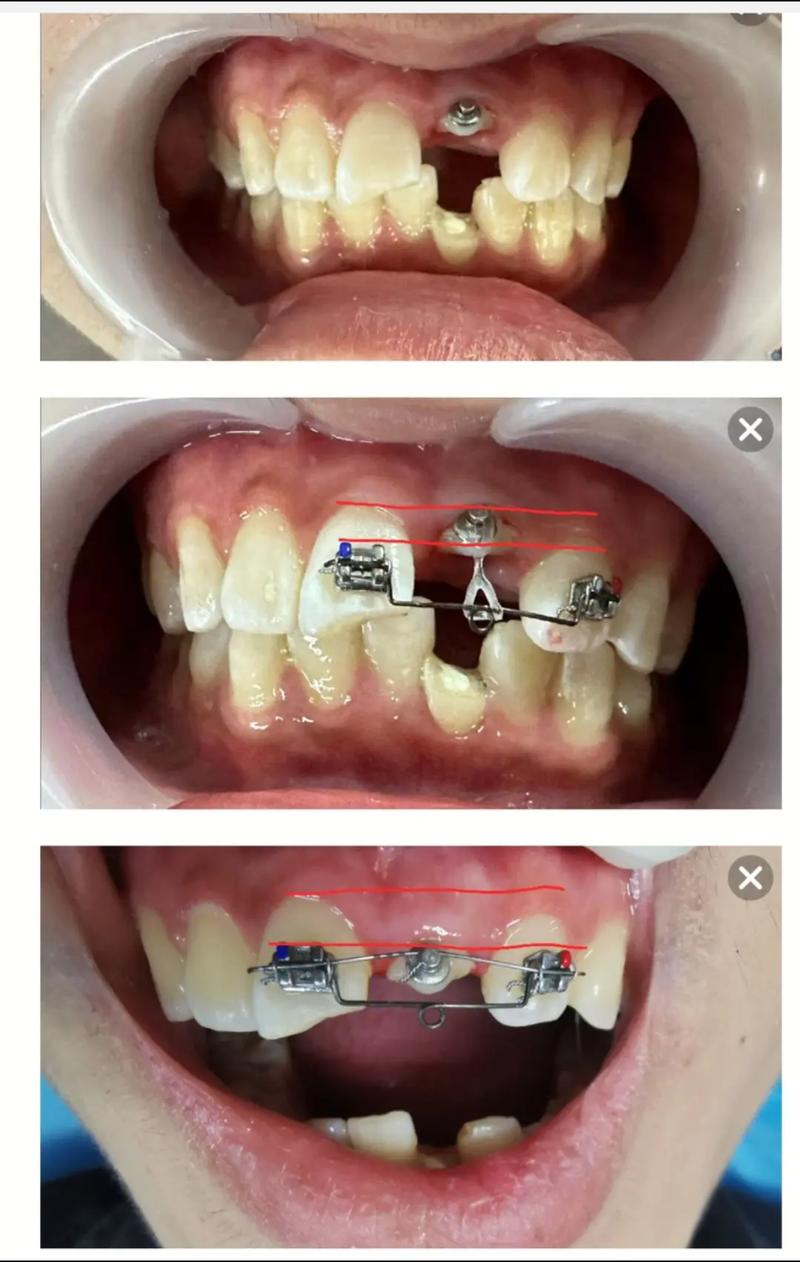

- 正畸辅助: 对于需要大量骨切除或牙齿位置不佳(如低位牙)的复杂病例,术前或术后进行正畸压低牙齿可以显著减少骨切除量,降低牙龈退缩风险,提高美学效果。